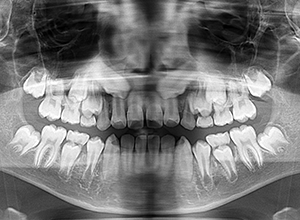

| パノラマ所見 | 上顎左右側犬歯は近心傾斜し側切歯歯根に重なるように認められた。 |